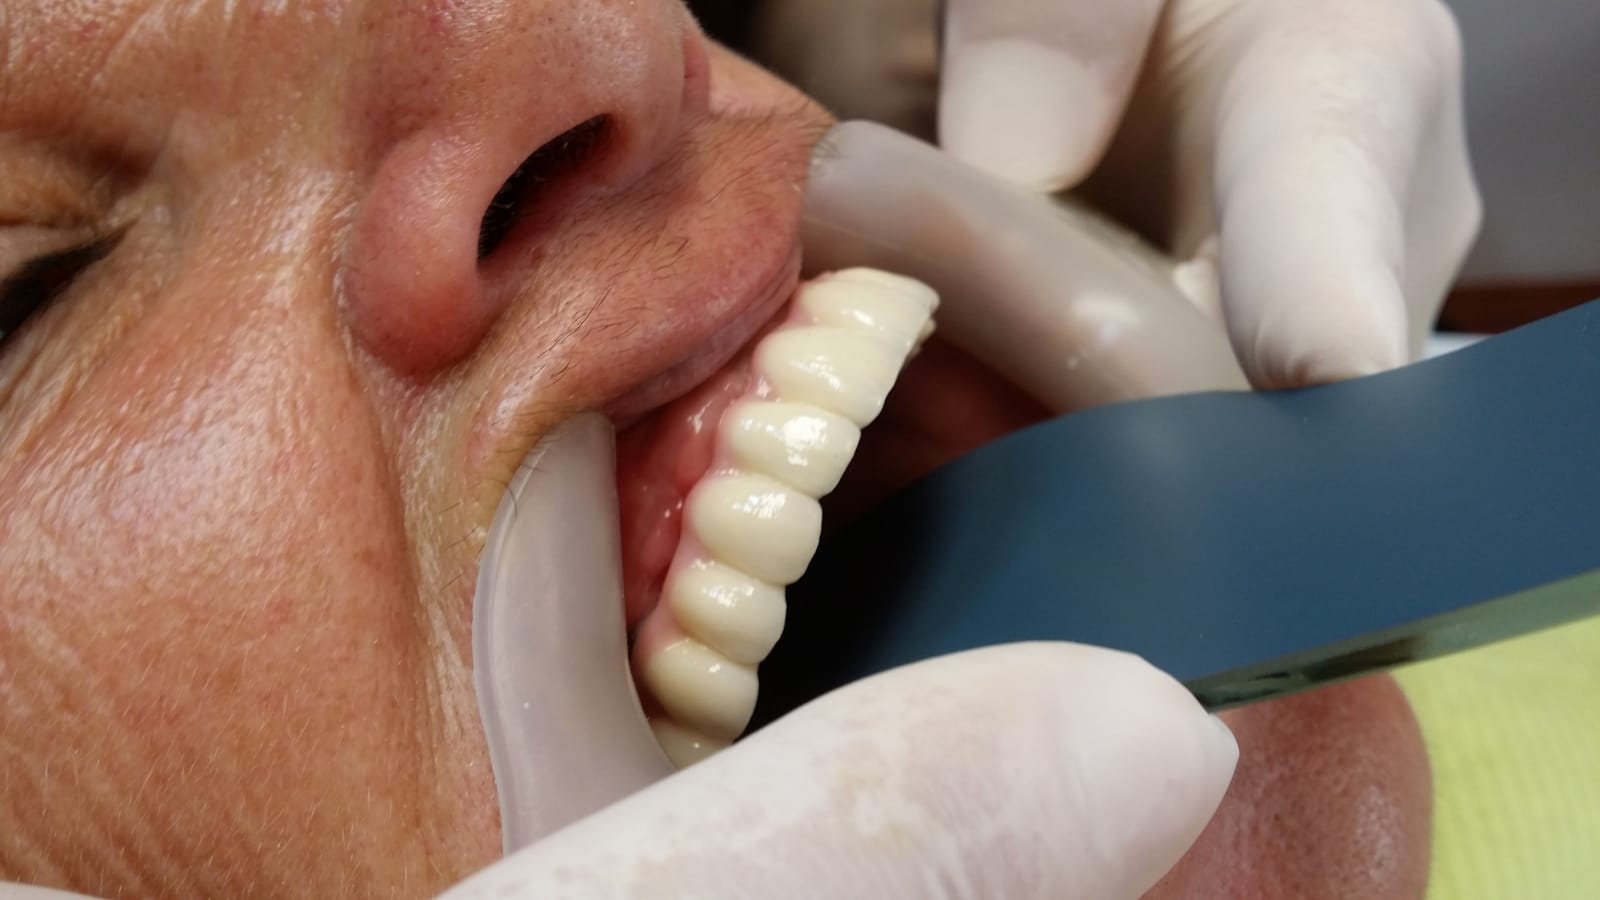

Punte fixa provizorie realizată la mandibula în 24 ore, pe 4 implanturi dentare

Reabilitare mandibulara pe sistem Fast and Fixed in 24 ore